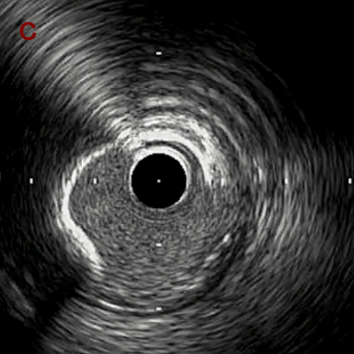

IVUS after OAS low speed 3回

IVUS imaging after low speed 3回

OAS low speedによる引きのsandingを3回行いIVUSを確認するとa-cでは心筋側側へのOASによる良好なbias変化と、それに伴いdの健常側への危険なbias変化を認めた。

そのためcでIVUSマーキングを行い、その点より引きで赤線のpinpoint OAS high speedを行い、dに関してはinjury回避のためにOASを当てない方針とした。